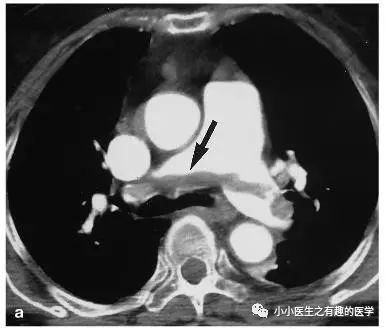

再来一个图。

仔细看,有端倪。

增强CT可以核实。

很明显,患者做了CT平扫,我们要仔细阅片,发现可疑,及时增强CT,要不然就漏诊了。